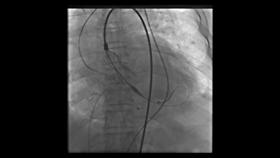

支架瓣膜植入释放

于爷爷家人商量后接受了这一方案。医生为他麻醉后,心脏大血管外科副主任李伟栋主任医师从他大腿根部穿刺,将一根粗细不到6毫米的导管携带人工瓣膜及装置,从血管一直送到心脏瓣膜处,缓慢旋转导管逐渐释放瓣膜,通过精细调控,植入的人工瓣膜如花瓣一样在于爷爷心脏上完美绽放,手术成功!